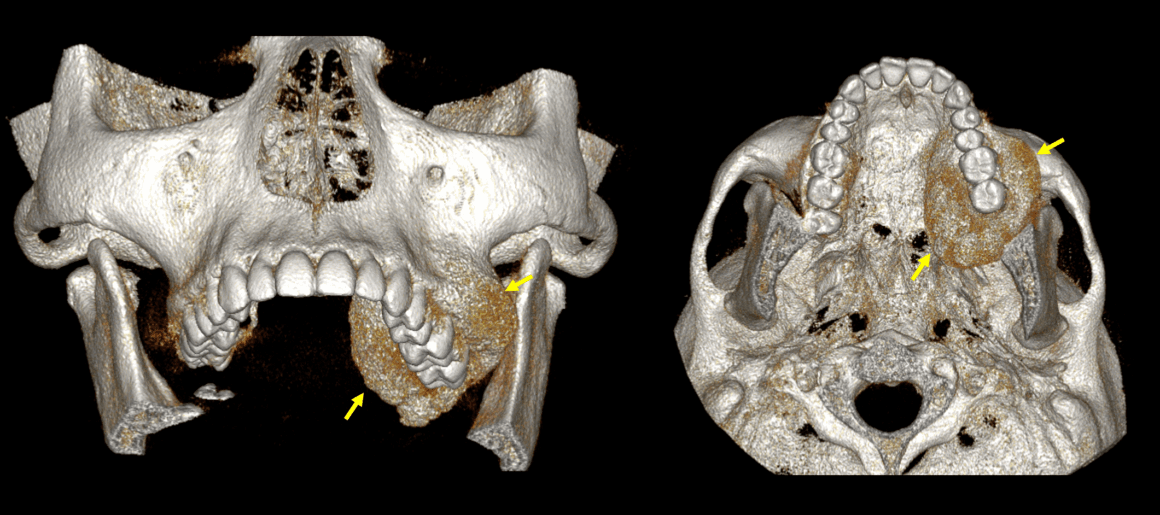

Fig.1

En la evaluación con tomografía computarizada cone beam, se realizó la reconstrucción panorámica del maxilar superior y los cortes transaxiales de algunas zonas dentales afectadas (Fig.1), donde se observa una imagen hiperdensa que se extiende tanto por vestibular como por palatino en el hueso alveolar y también condiciona el levantamiento del piso del seno maxilar izquierdo condicionando su ocupamiento parcial.